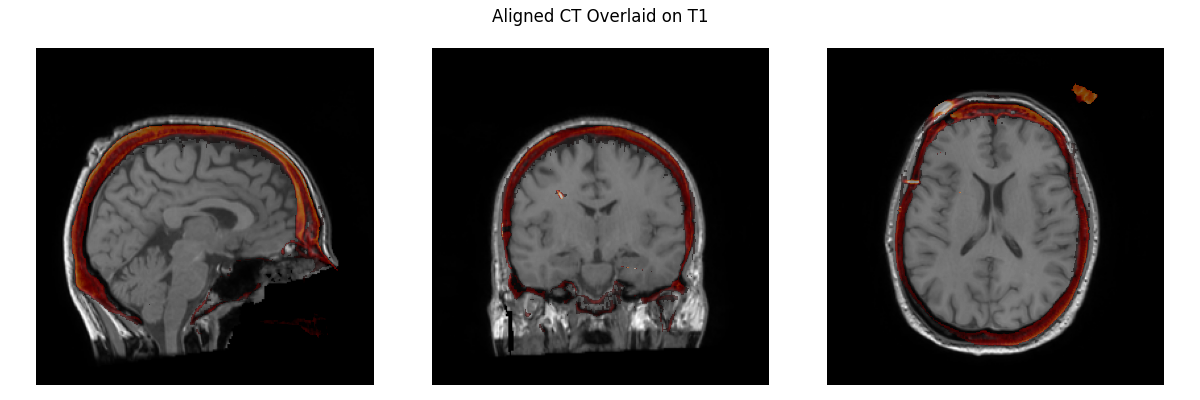

So this is what we have now: And this is what we have in I think it only differs by 1.2mm and 1.9 degrees from what you had before. I have a hard time seeing meaningful differences here, and if I didn't know which is which I'm not sure which I'd say was better, but I am no expert here! As much as I'm inclined to keep it, indeed we shouldn't keep something if you think it is "way off" even if I can't see it. I thought you had said before that the MR-CT was now okay, but since it's not I agree perhaps the easiest thing to do is just to revert to the old affine and commented out code for the MR-CT step, and revisit sometime later how to use our standard pipeline to get an affine of equivalent quality. |

Way off is a relative term and I think you have to spend some time aligning these by hand to appreciate when the fit is right and when it's not. 1.2 mm and 1.9 degrees isn't a whole lot but those are clearly how much it's wrong and to me, that's too much. You can align by eye closer than that, the whole point of this is that it should be as precise as possible with the alignment, better than what can be done by human eye. I could fix the top image to be much closer by hand. |

Keep in mind that you're only seeing a bit of the alignment with the three slices and in a viewer like freeview it would be much more obvious how much the alignment is actually off and I would consider the first alignment to be poor and need fixing if someone had done it by hand and I was reviewing it and the second alignment would be good. |